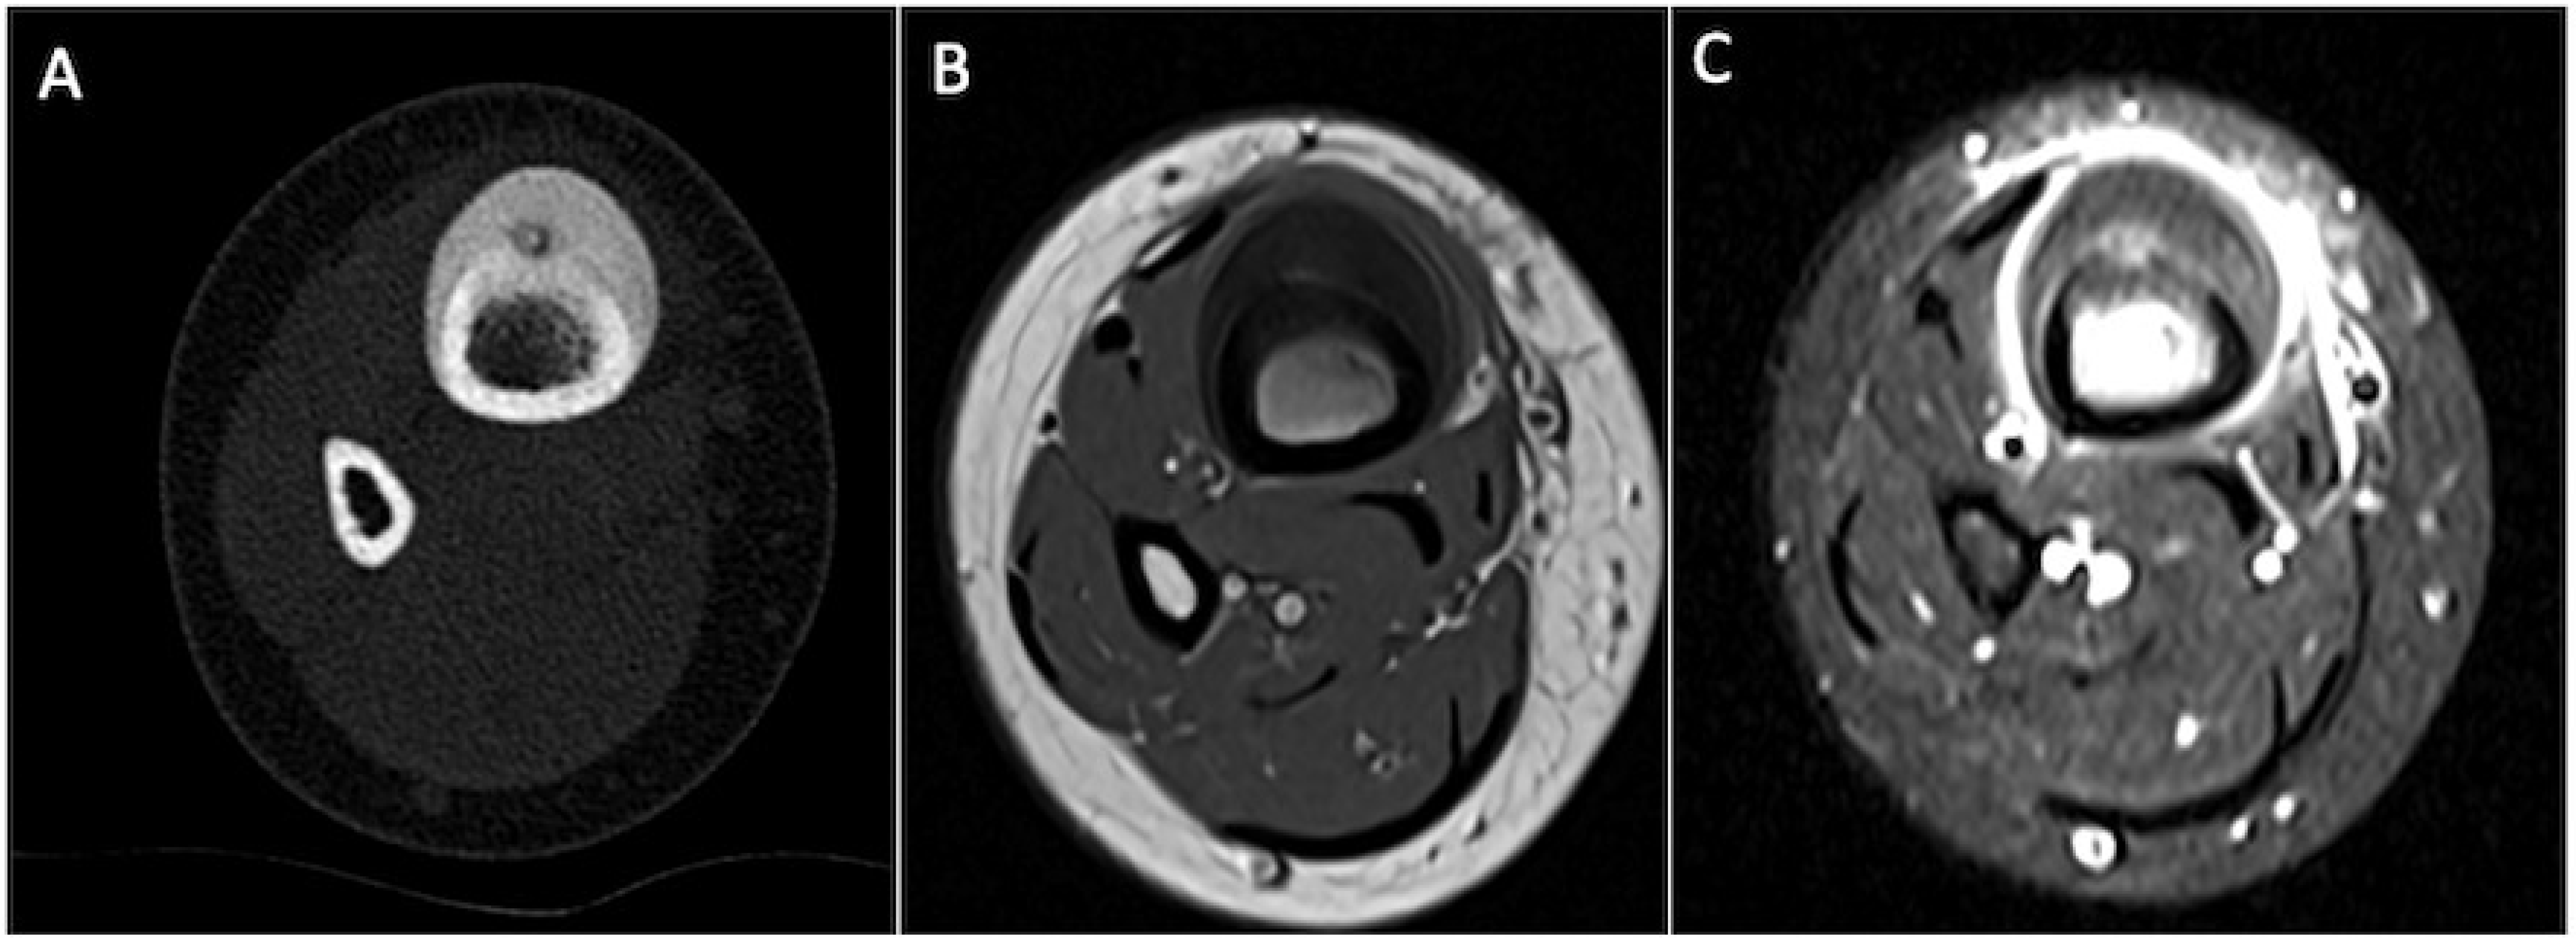

5.2. Osteoid Osteoma

- Tepelenis, K.; Skandalakis, G.P.; Papathanakos, G.; Kefala, M.A.; Kitsouli, A.; Barbouti, A.; Tepelenis, N.; Varvarousis, D.; Vlachos, K.; Kanavaros, P.; et al. Osteoid Osteoma: An Updated Review of Epidemiology, Pathogenesis, Clinical Presentation, Radiological Features, and Treatment Option. In Vivo 2021, 35, 1929–1938. [Google Scholar] [CrossRef] [PubMed]

- Carneiro, B.C.; Da Cruz, I.A.N.; Filho, A.G.O.; Silva, I.P.; Guimarães, J.B.; Silva, F.D.; Nico, M.A.C.; Stump, X.M.G.R.G. Osteoid osteoma: The great mimicker. Insights Imaging 2021, 12, 32. [Google Scholar] [CrossRef]

- Klontzas, M.E.; Zibis, A.H.; Karantanas, A.H. Osteoid Osteoma of the Femoral Neck: Use of the Half-Moon Sign in MRI Diagnosis. Am. J. Roentgenol. 2015, 205, 353–357. [Google Scholar] [CrossRef]